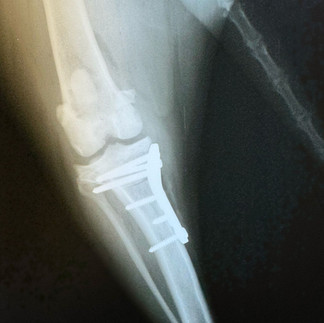

Siamo lieti di presentare alla nostra clientela la nuova Radiologia Digitale Diretta ad alta definizione, in grado di offrire ai nostri pazienti una diagnostica per immagini ancora più affidabile e sicura, soluzione che bypassa le limitazioni delle tecnologie precedenti. La nuova radiologia digitale rappresenta un avanzamento significativo rispetto al passato consentendo una diagnosi più rapida e precisa.

Le immagini vengono acquisite, visualizzate e archiviate in formato elettronico in modo da permettere una gestione più efficiente dei dati migliorando così la cura dei nostri animali.